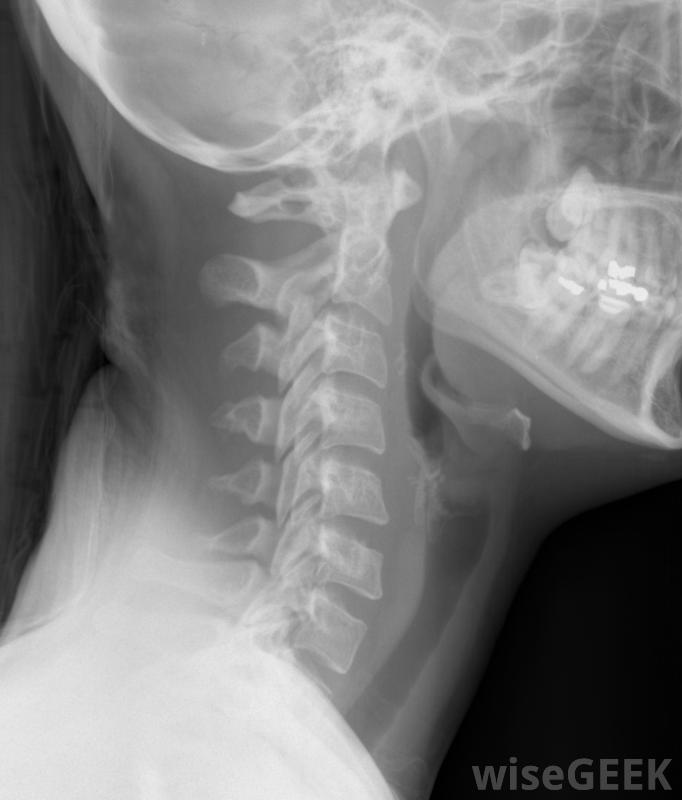

颈椎病通常可以通过改变生活方式等保守措施进行治疗,体育锻炼,有时使用非甾体抗炎药(NSAIDs)。只有在严重的情况下,这些保守措施没有反应,才需要手术。每个病人最好的颈椎病治疗应该由医学专家根据患者的临床病史来选择阿米替林通常用于治疗抑郁症,但在治疗颈椎病时也被证明是有效的颈椎病表现为颈肩痛,多为脊椎骨因磨损而自然老化所致,多见于55岁以上人群,骨质磨损、椎体间垫或椎间盘退变,可能会引起疼痛。更严重的情况下,神经根可能会受到压迫,非常严重的情况下可能会累及脊髓,可能影响手臂和腿部。颈部X光片,包括颈椎颈椎病最好的治疗方法应该根据症状来制定,通常症状会自行消失,但复发是常见的最初的症状通常是颈部和肩部疼痛,可以通过布洛芬等非甾体抗炎药和/或肌肉松弛剂(如环苯扎滨)进行急性治疗。阿片类药物可能需要在急性疼痛的情况下使用,但由于这些药物有滥用的可能,因此不鼓励长期使用严重的颈椎病患者可使用加巴喷丁治疗,最好的颈椎病治疗方法可能是长期使用小剂量阿米替林。一些研究表明,其他用于治疗慢性疼痛的药物,如普瑞巴林、加巴喷丁和度洛西汀都是有效的。在无反应的情况下,医生可能会推荐手术作为颈椎病的治疗方法。颈神经根病就是手术在被挤压的神经上进行预处理,以释放神经。颈椎病的外科治疗很少见,由于这种情况通常治疗得比较保守。按摩可能有助于减轻颈椎病带来的疼痛通常,颈椎病的治疗包括改变生活方式和锻炼等非药物措施。消除诸如剧烈运动或剧烈运动、办公室不良姿势或反复劳累等诱因是至关重要的。通常建议使用颈托或牵引固定颈部低冲击运动,如散步或游泳是非常有益的。针灸可能有助于减轻颈椎病带来的疼痛理疗师或理疗师可以推荐颈部和肩部强化运动。按摩,针灸和热敷或冷敷也有助于减轻疼痛。任何手法或运动都应小心进行,如果引起疼痛加剧,应停止。在大多数情况下,遵循保守的建议可以解决颈椎病颈椎病表现为颈肩部疼痛。颈椎病的治疗可能需要手术颈椎病引起的疼痛可以通过使用凝胶包暂时缓解。患者患有颈椎病的患者应咨询医学专家,确定最佳治疗方案。